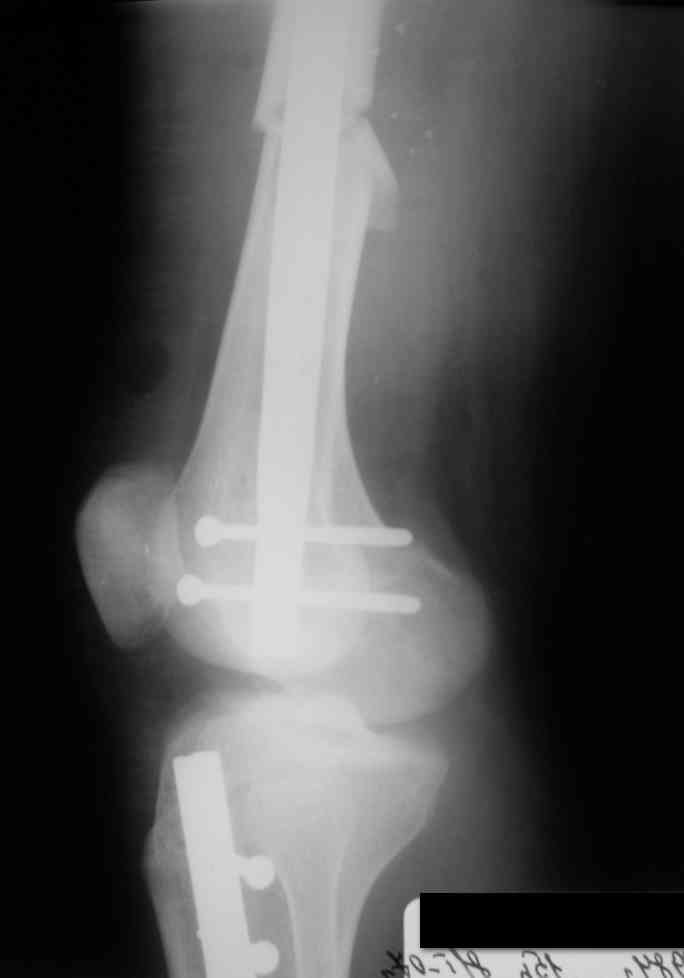

Дорогой Александр. Имею скромный опыт использования системы Fixion при

переломах плеча, бедра и тибии. Всего 18 наблюдений с сентября 2007

г.Результаты отличные. Гвоздь индивидуален для каждого медулярного

канала. Легко имплантируется как в узкий, так и в деформированный

канал. Это позволяет применять метод интрамедулярного остеосинтеза без

ненужных потерь времени операции, флюороскопии и реально снижает

крвопотерю и операционный риск. Удаление происходит без проблем.

Особенно интересны больные с ипсилатеральными переломами бедра и голени.

В отношении ранней нагрузки при спиральных переломах лучше не

торопиться. По данному случаю необходимо достигнуть исчезновения щели

между штифтом и внутреним кортексом по Rg. А так картинка прекрасная -

и длина сегмента и репозиция. Можно поздравить, коллега!